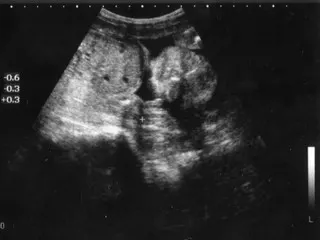

ジュニアの頭長5.7cm、体重645g。

超音波で見てるとき、いつもみたいに動かないなぁと思っていたら、

どうやらガッツリ寝ていたみたいで;;

↑この表情のまま微動だにせず 笑。

呑気な寝顔が可笑しくて、笑ってしまいました。